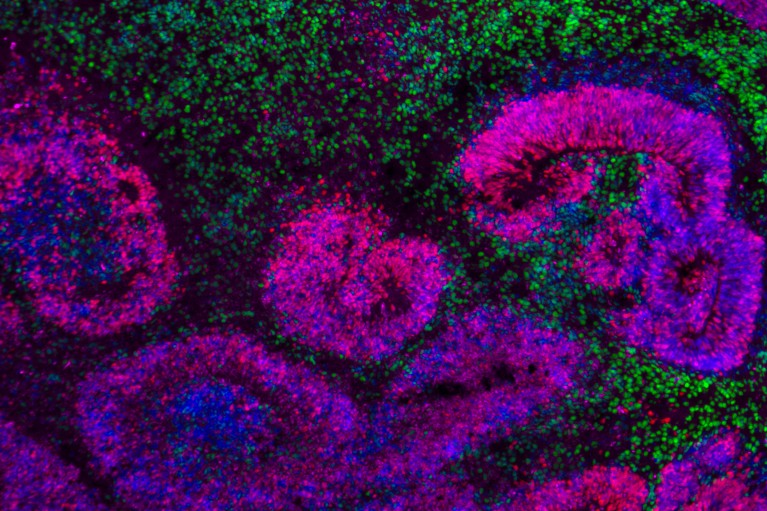

A set of five papers published in Nature (5 November 2025) presents the most detailed atlases to date of how mammalian cortical cells arise from stem cells during embryonic development and early life. Researchers tracked hundreds of thousands of individual cells in mouse and human cortexes, charting molecular events, lineage relationships and timing for when progenitor cells make excitatory neurons, inhibitory neurons and supporting glial cells. The work is part of the BRAIN Initiative Cell Atlas Network (BICAN) and provides a high-resolution reference for developmental neuroscience.

The collection includes two major mouse studies and human embryonic analyses. Hongkui Zeng’s team produced a comprehensive developmental atlas of the mouse visual cortex from embryonic day 11.5 to 56 days postnatal, revealing ongoing postnatal neuronal specialisation. Tomasz Nowakowski and colleagues used DNA barcoding in human fetal tissue to reconstruct lineage trees, demonstrating a clear temporal switch in progenitor output from excitatory to inhibitory neurons around the 20-week mark. Across the papers, investigators capture precise molecular signatures and developmental programmes that underpin cell-type emergence in the cortex.